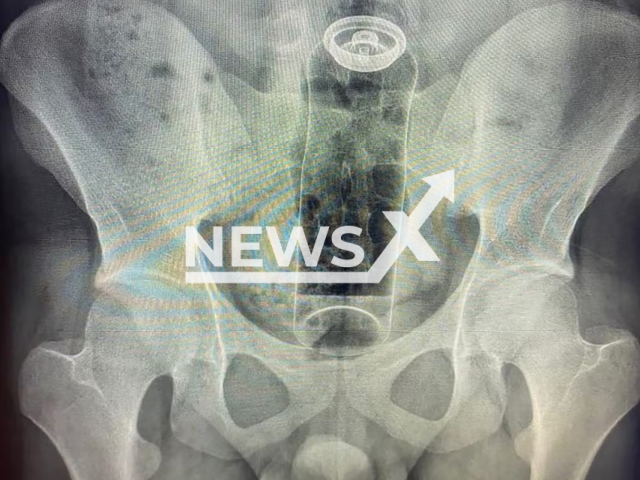

An x-ray image shows the deodorant stuffed in the bum, undated. A 19-year-old patient had inserted the item during a sexual game. Note: Private photo. (Newsflash) An x-ray image shows the deodorant stuffed in the bum, undated. A 19-year-old patient had inserted the item during a sexual game. Note: Private photo. (Newsflash)